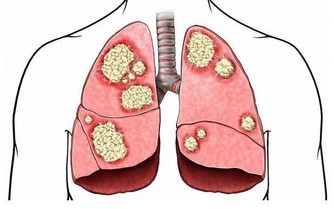

據研究顯示,抽煙是當今社會導致肺癌的罪魁禍首之一。約40%的慢性阻塞性肺病由吸煙直接引起。吸煙指數(每天吸菸支數×菸齡)大於400者,患肺癌的機率將升高7倍之多。而對於長期吸二手煙的人來說,患肺癌的機率將會提高25%以上。

戒菸3~9個月後:呼吸問題變好了,肺部開始逐漸恢復健康。

戒菸10年後:患肺癌的機率達到了正常吸煙人的一半。